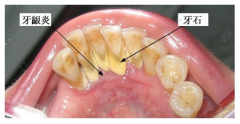

生活中如何预防牙结石的堆积

对于口腔卫生不太注意或者不注意控制饮食的人群,随着年龄的增长很多人都会出现牙齿表面牙结石堆积的情况。而牙结石的危害多数人都不了解,牙龈炎牙周病都是因为牙结石这样的局部刺激一步步导致......[阅读全文]